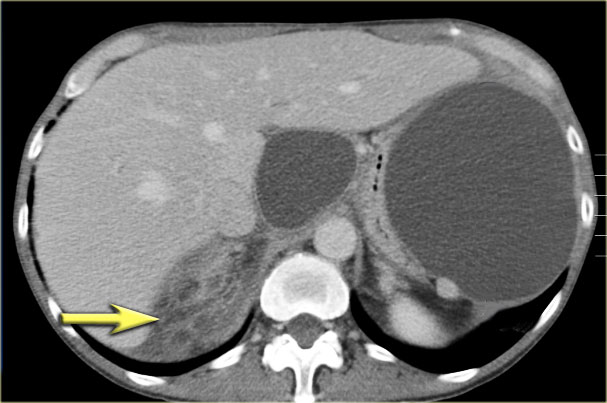

CT demonstrates two large cysts in a 45 year old woman, who had a trauma (fig).

Notice some fat stranding in the retroperitoneal space (arrow).

The imaging findings combined with the history make it very likely that these are traumatic pseudocysts.